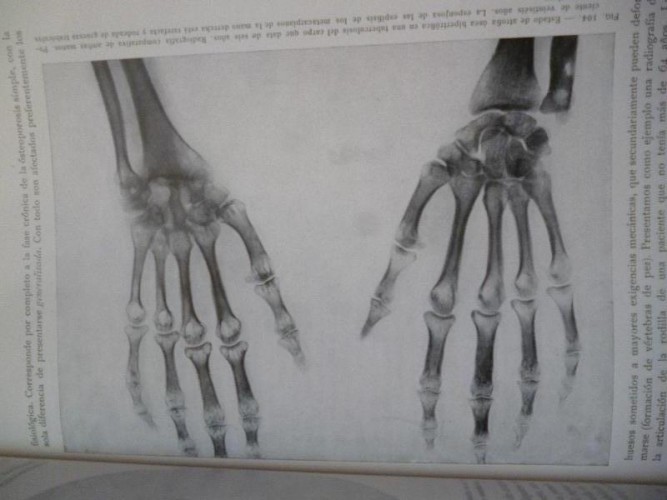

Muy ilus. con radiografías.